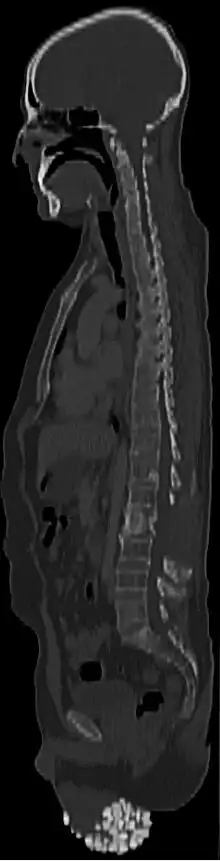

![]() | |